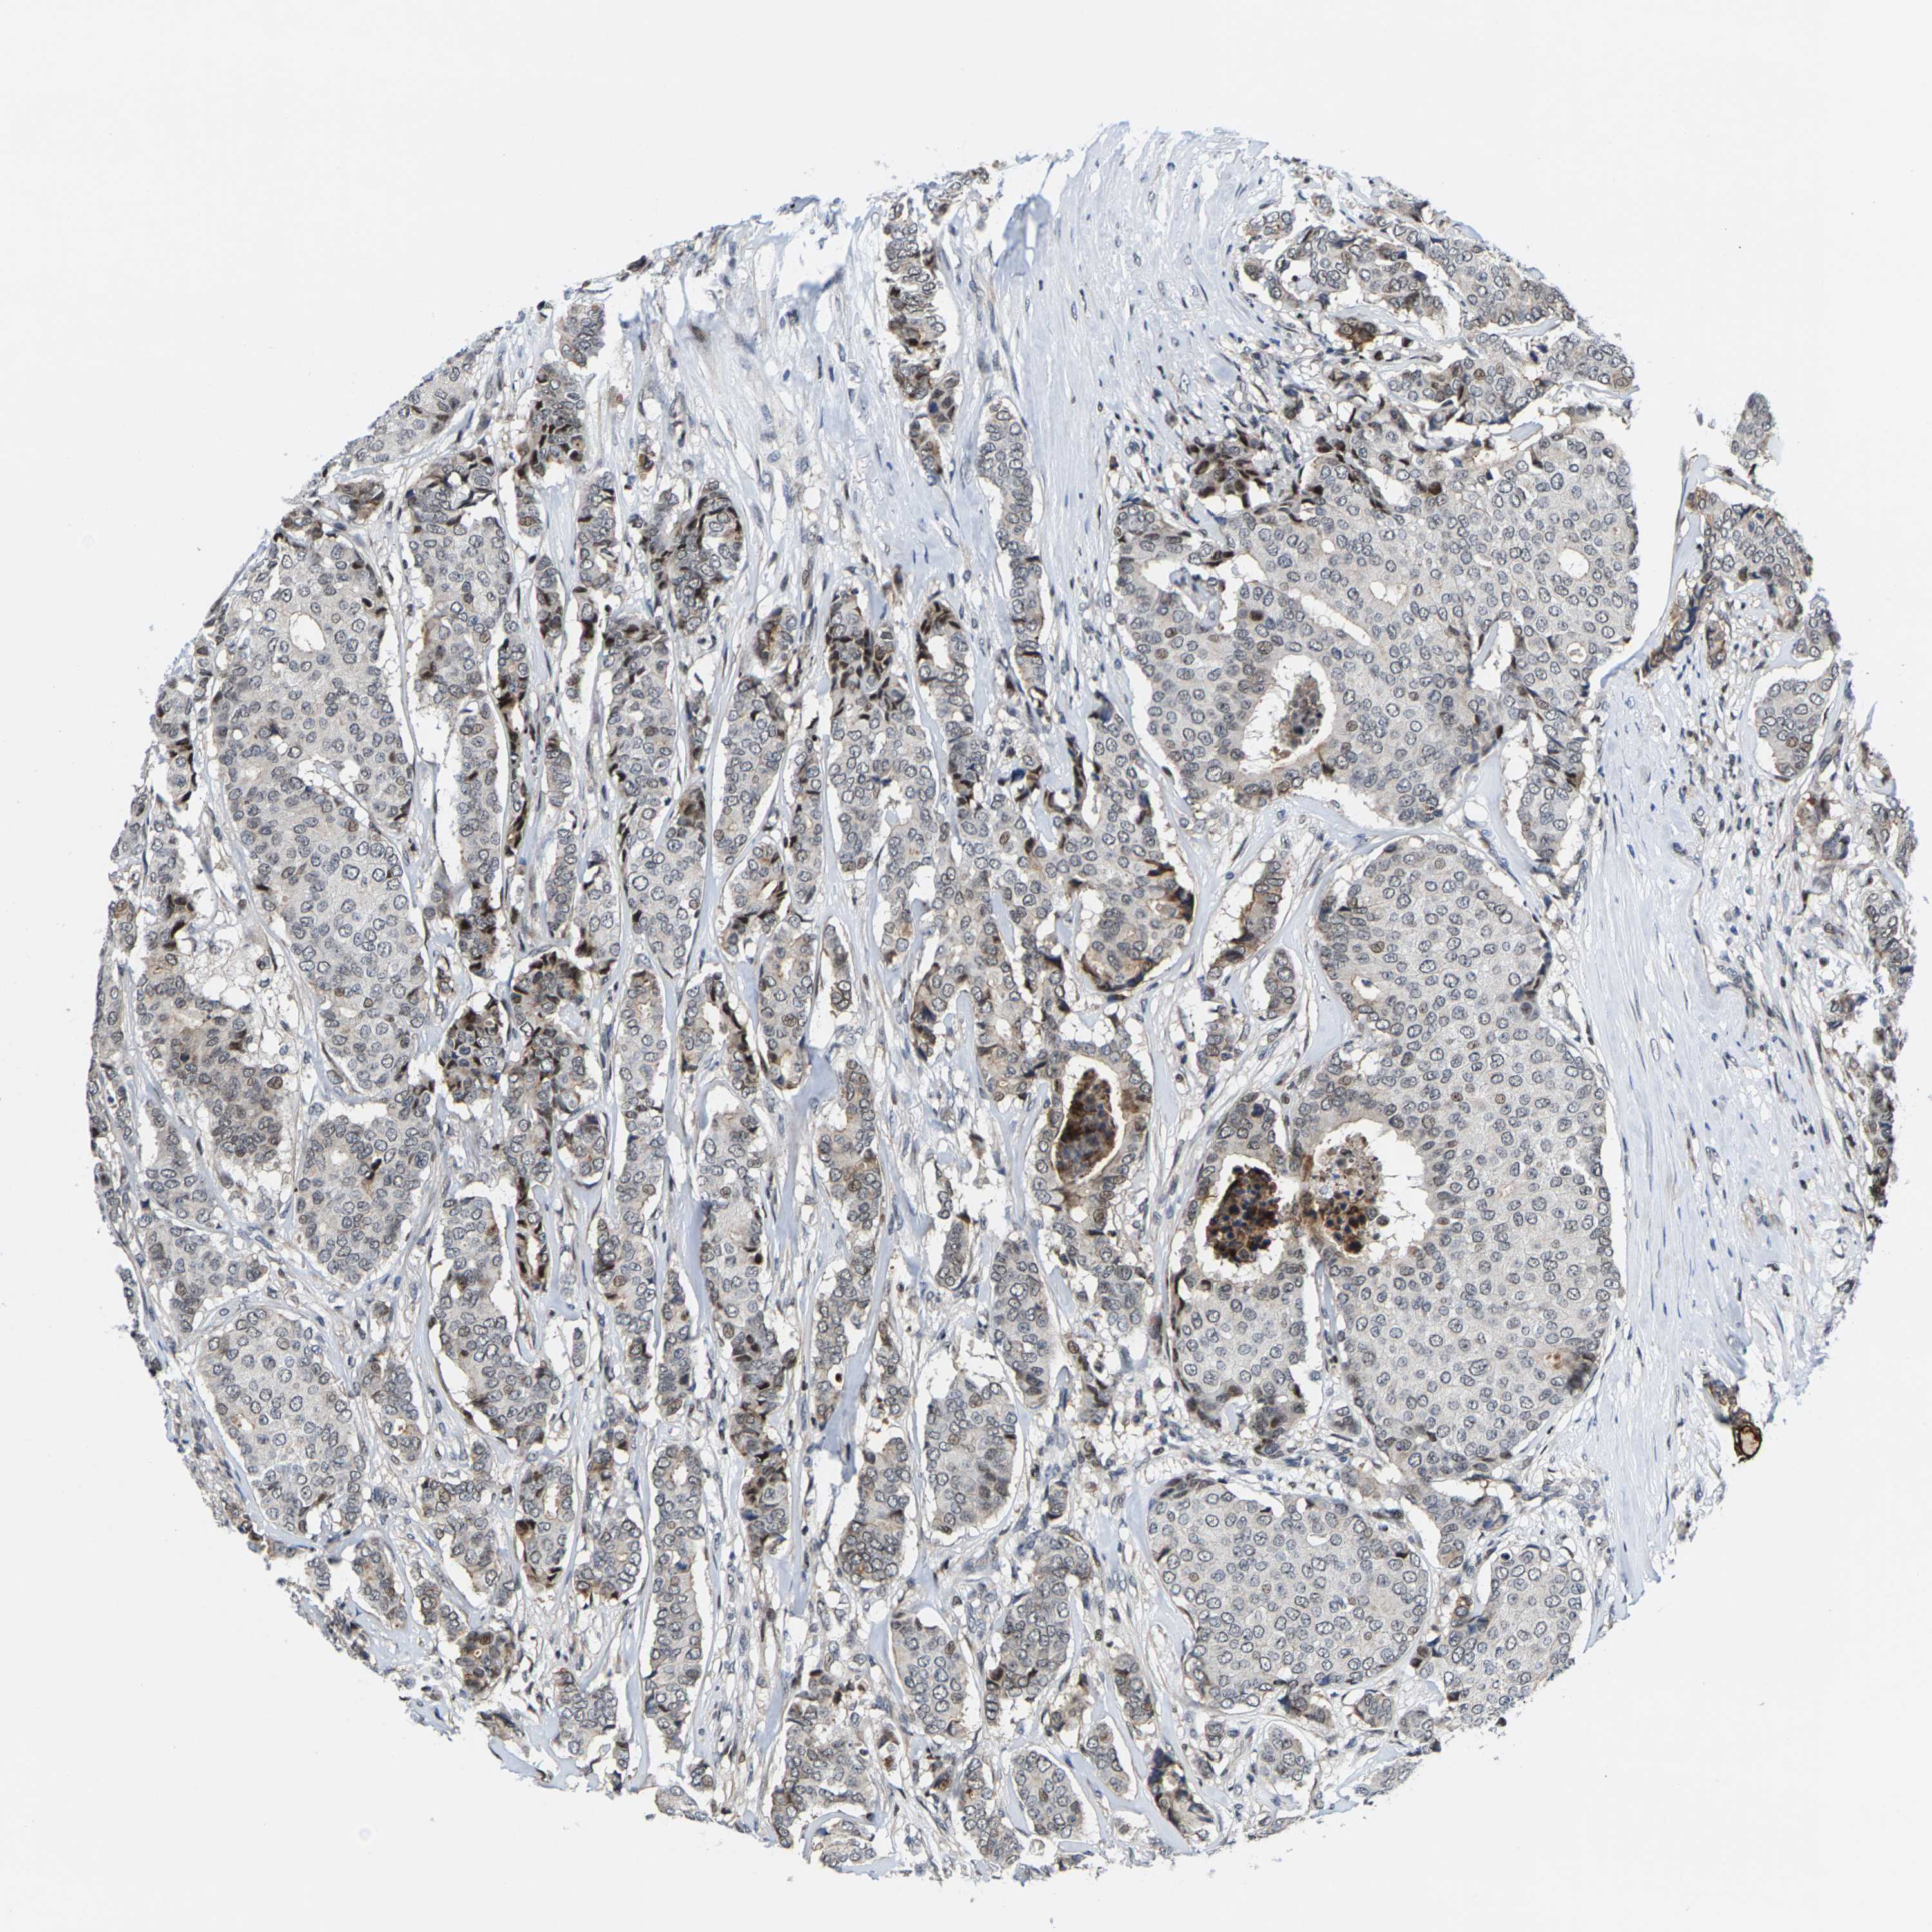

CANCER BREAST CANCER Show tissue menu

BRCA TCGA BRCA VALIDATION PROTEIN EXPRESSION